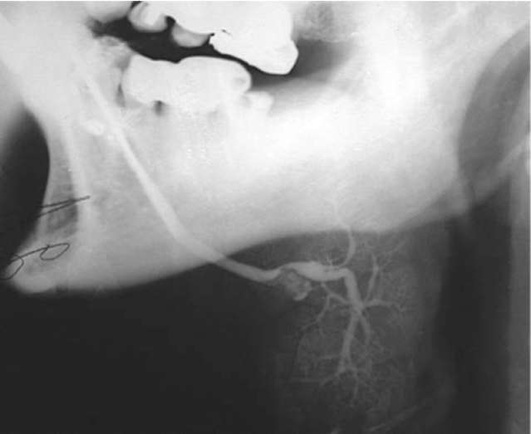

Диагностика. В распознавании слюннокаменной болезни имеет значение не только обнаружение камня, но и выявление причины камнеобразования. Анамнестический признак в виде слюнной колики в 99% случаев позволяет предположить наличие конкремента. На обзорных рентгенограммах рентгеноконтрастные камни хорошо визуализируются (рис. 6.11-6.13), на сиалограммах они видны в виде очага дефекта наполнения контрастного вещества. На эхосиалограммах камни видны по типу «звуковой дорожки». Особенно часто (более чем в 99%) камни выявляются на компьютерных томограммах.

image

Рис. 6.11. Рентгенограмма черепа в прямой проекции. В области левой околоушной железы определяется конкремент

Рис. 6.12. Рентгенограмма нижней челюсти в боковой проекции. В области левой поднижнечелюстной железы определяется конкремент